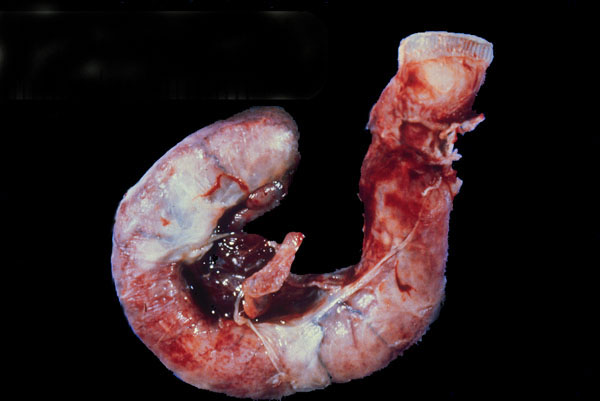

Acute appendicitis

The vermiform appendix swollen and hemorrhagic focally and is covered with whitish

fibrin

.